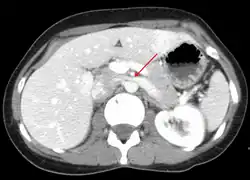

The nutcracker syndrome results from compression of the left renal vein between the aorta and the superior mesenteric artery.

Compression most commonly occurs between the abdominal aorta (AA) and superior mesenteric artery (SMA), though compression may also occur between the aorta and spine.[3][1] Risk factors include retroperitoneal cancers, abdominal aortic aneurysm, low body mass index, lordosis, and enlarged lymph nodes around the aorta.[1] Diagnostic may be suspected based on symptoms and confirmed by medical imaging after ruling out other possible causes.[1] Superior mesenteric artery syndrome is a different condition in which the duodenum is compressed between the the SMA and AA.[4]

In normal anatomy, the LRV travels between the SMA and the AA.[11] Occasionally, the LRV travels behind the AA and in front of the spinal column. NCS is divided based on how the LRV travels, with anterior NCS being entrapment by the SMA and AA and posterior NCS being compression by the AA and spinal column.[11] NCS can also be due to other causes such as compression by pancreatic cancer, retroperitoneal tumors, and abdominal aortic aneurysms.[11] Although other subtypes exist, these causes are more uncommon in comparison to entrapment by the SMA and the AA.[11] Patients with NCS have a tendency to have a tall and lean stature, as this can lead to a narrower gap between the SMA and the AA for the LRV. [14]

Nutcracker syndrome is diagnosed through imaging such as doppler ultrasound (DUS), computed tomography (CT), magnetic resonance imaging (MRI), and venography.[15] The selection of the imaging modality is a step-wise process. DUS is the initial choice after clinical suspicion based on symptoms. CT and MRI are used to follow up afterwards, and if further conrfirmation is necessary, venography is used to confirm.[15]

CT and MRI

CT and MRI can be used afterward to confirm compression by the AA and SMA with comprehensive measurements of the abdominal vasculature. A "beak sign" can often be seen in CT scans due to the LRV compression. However, CT and MRI cannot demonstrate the flow within the compressed vein. These two modalities can be used to confirm other evidence for NCS such as back-up of blood flow into the ovarian veins.[14][9]